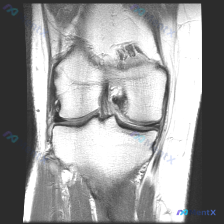

整理了一份很有参考意义的影像读片病例,核心问题是:这张膝关节MRI-T1序列矢状位图像上,能观察到软骨异常吗?把整个分析思路分享给大家。 一、影像基础信息 这是一幅标准的膝关节矢状位T1加权像,图像对比度良好,骨髓腔呈正常高信号(脂肪髓),皮质骨呈低信号,解剖结构显示清晰,无明显运动或金属伪影;图像...

刚整理了一份有意思的膝关节MRI读片病例,临床提示观察到软骨异常,但单张T1加权矢状位影像却没看到明确异常,把分析思路整理出来和大家讨论。 一、病例基本影像信息 这是一张膝关节T1加权矢状位旁矢状位MRI图像,显示区域包括股骨远端、胫骨近端、髌骨、髌腱、Hoffa's脂肪垫和部分后交叉韧带,主要观察...

今天遇到一个有意思的读片问题:临床怀疑膝关节软骨异常,但提供的单张矢状位T1加权MRI读下来基本正常,整理一下分析思路和大家分享。 一、现有病例影像资料整理 这是一张膝关节矢状位T1加权MRI,图像质量清晰,信噪比良好,可见层面包含股骨远端外侧髁、胫骨近端、后交叉韧带、半月板前后角、髌韧带及Hoff...